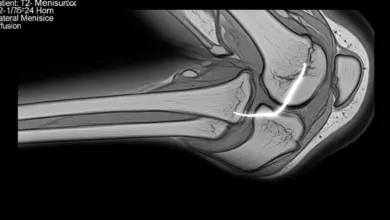

Boa parte do sucesso está no planejamento. Radiografias panorâmicas com carga, estudo do eixo mecânico, análise do grau de deformidade e definição do ponto de correção fazem parte dessa etapa.

- Integridade meniscal.